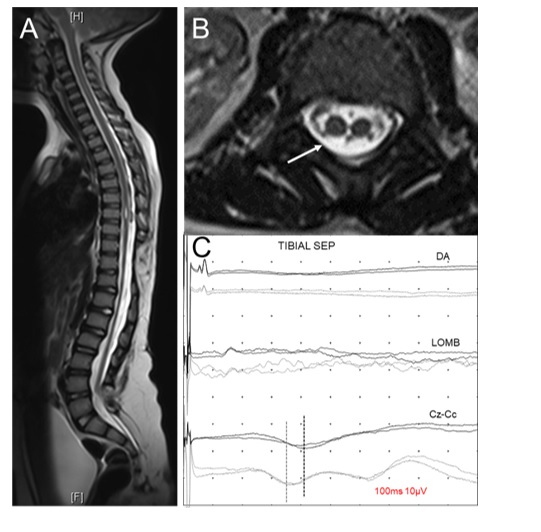

Şekil 13. Multipl

skleroz tanılı kırk bir yaşındaki erkek hastanın sagital

(A) ve transversal (B) planda T2 MR

kesitlerinde servikal omuriliğin sol posterior parasantral

kesimini tutan, demiyelinizan bir lezyon

görülmektedir (oklar). Sağ n. medianusun bilekten

uyarılmasıyla normal latans ve amplitüdlü

periferik (1. trase), spinal

(2. ve 3. trase) ve kortikal (4. trase)

yanıtlar kaydedilmiştir (C) Sol taraf uyarımı ile periferik ve kortikal

potansiyeller normal olarak kaydedilirken servikal potansiyeller elde

edilememiştir (D). Bu hastanın tibial SEP incelemesinde iki yanlı normal

ve simetrik periferik, spinal ve kortikal yanıtlar

kaydedilmiştir.